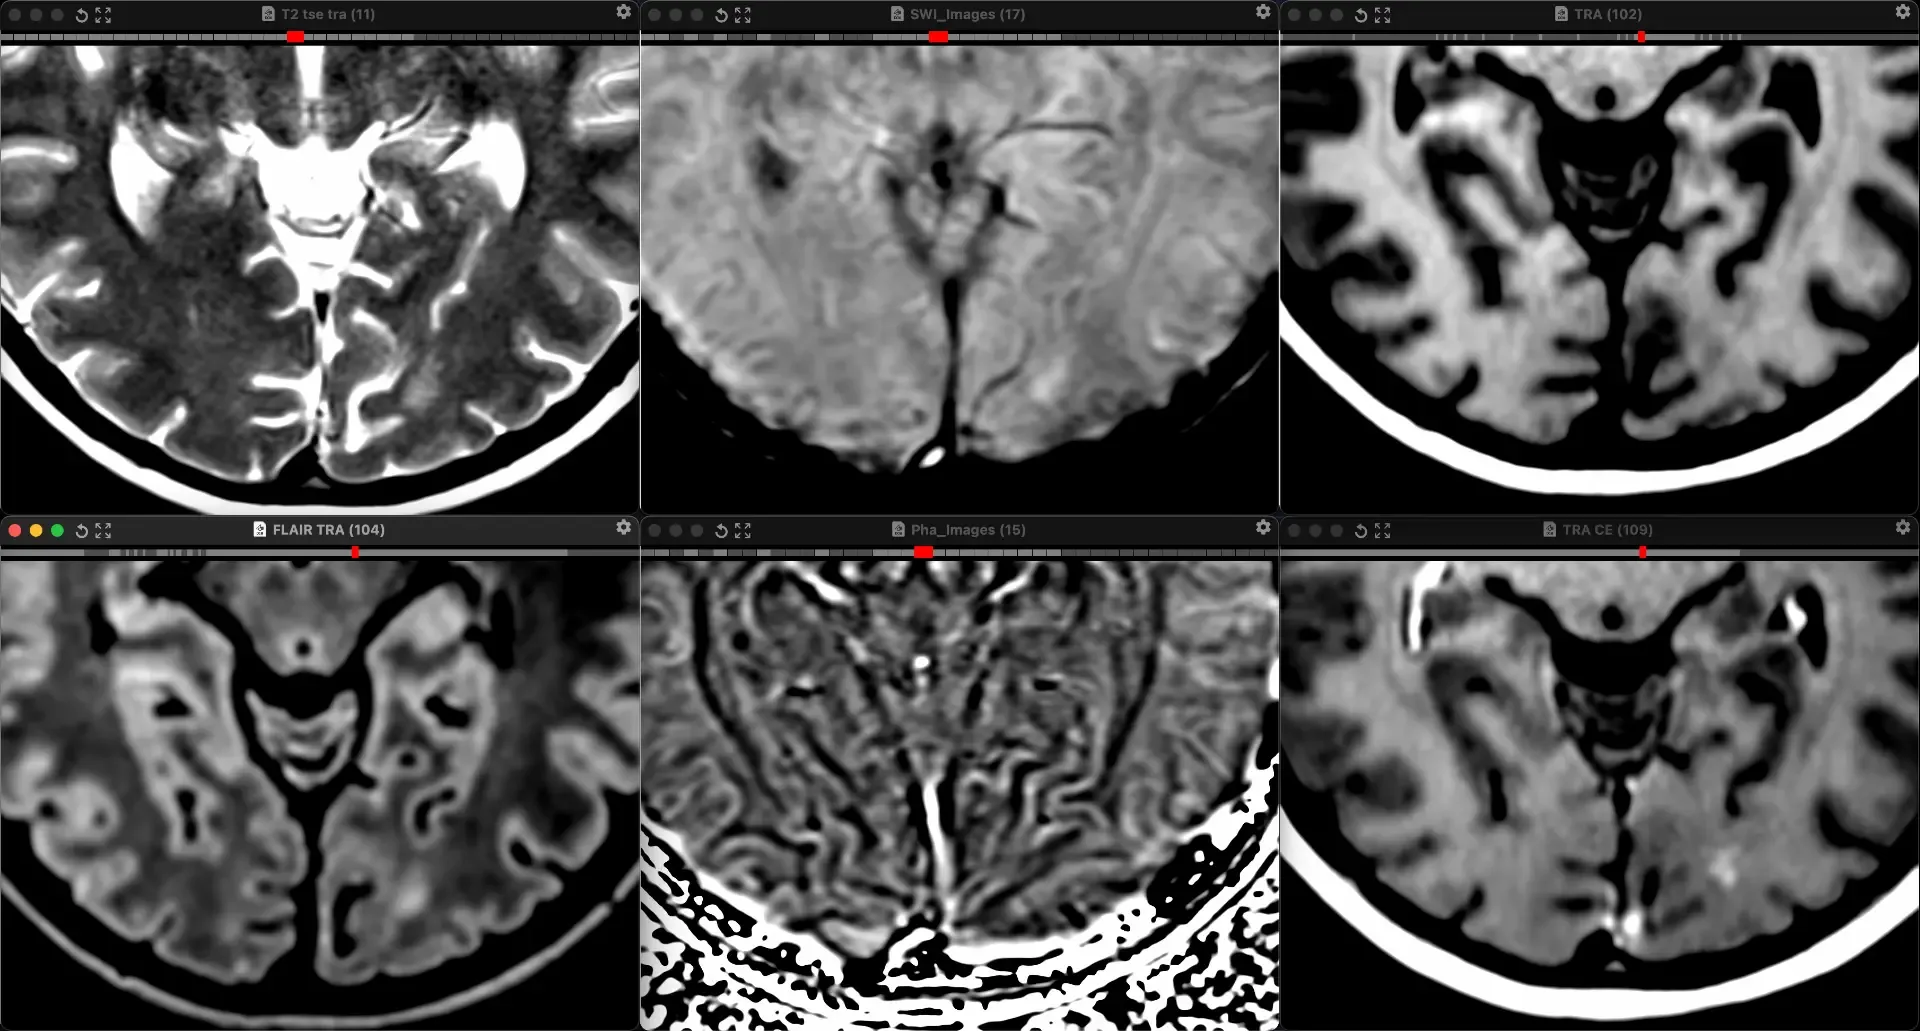

Клинический случай кавернозной мальформации, ассоциированной с венозной аномалией развития (ВАР). Следует напомнить, что ВАР часто сочетаются с каверномами, однако точные статистические данные не привожу, чтобы простимулировать самостоятельный поиск информации и закрепление знаний. Клиническая симптоматика у данного пациента отсутствует, что является типичным сценарием для подобных находок. Диагноз установлен случайно.

Женщина 32 года. Больной считает себя с 2024 г, когда стала отмечать онемение угла рта. Со слов пациентки ей был предварительно выставлен диагноз - РС, но дополнительных методов обследования и специфического лечения не проводилось. В настоящее время жалоб нет. В исследовании от октября 2024 отмечался очаг в левой затылочной доле с выраженным контрастированием, в настоящее время этот же очаг отмечается с сохраняющимся контрастированием. Формально - есть выполнение критериев диссеминации и в пространстве (юкстакортикальный и перивентрикулярный очаги есть), и во времени (есть усиливающиеся и неу…